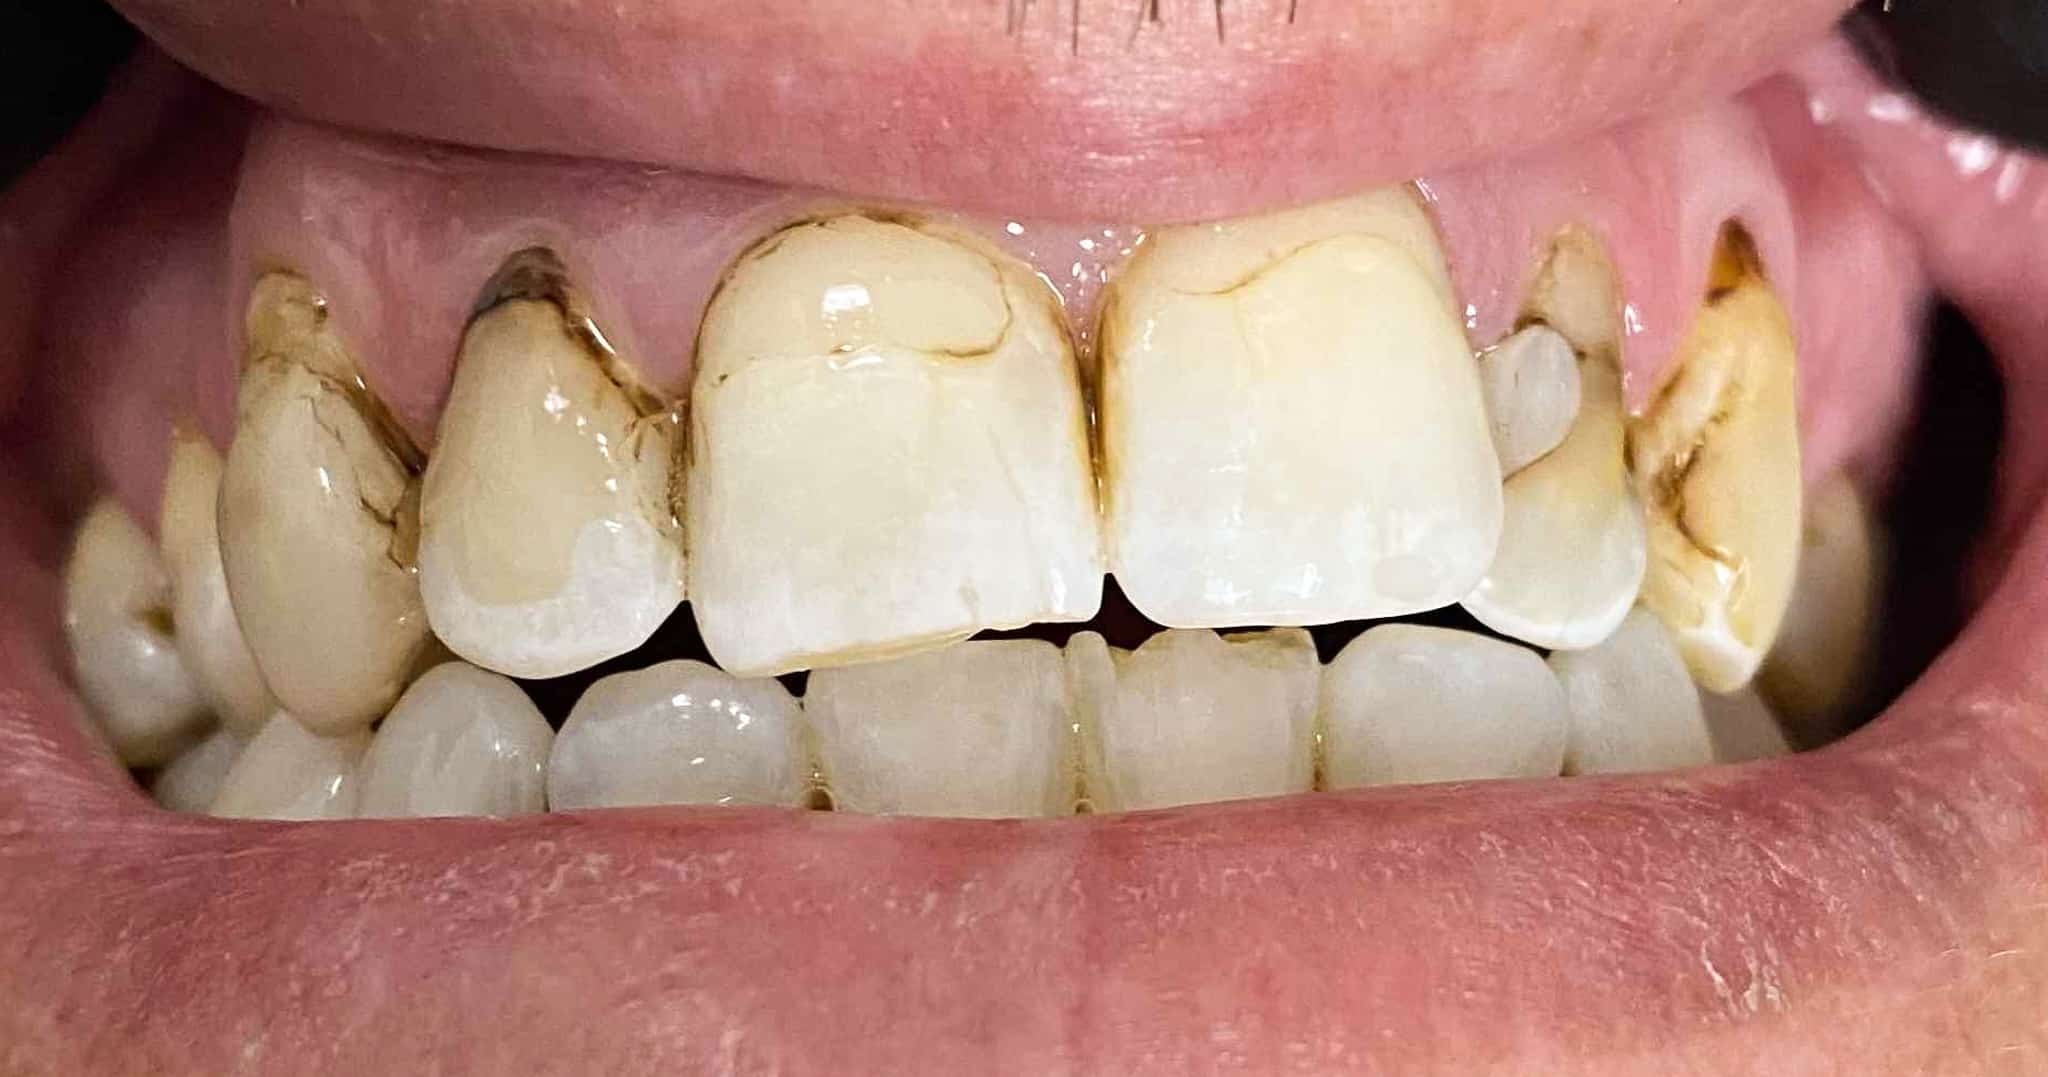

Before and After Image Gallery